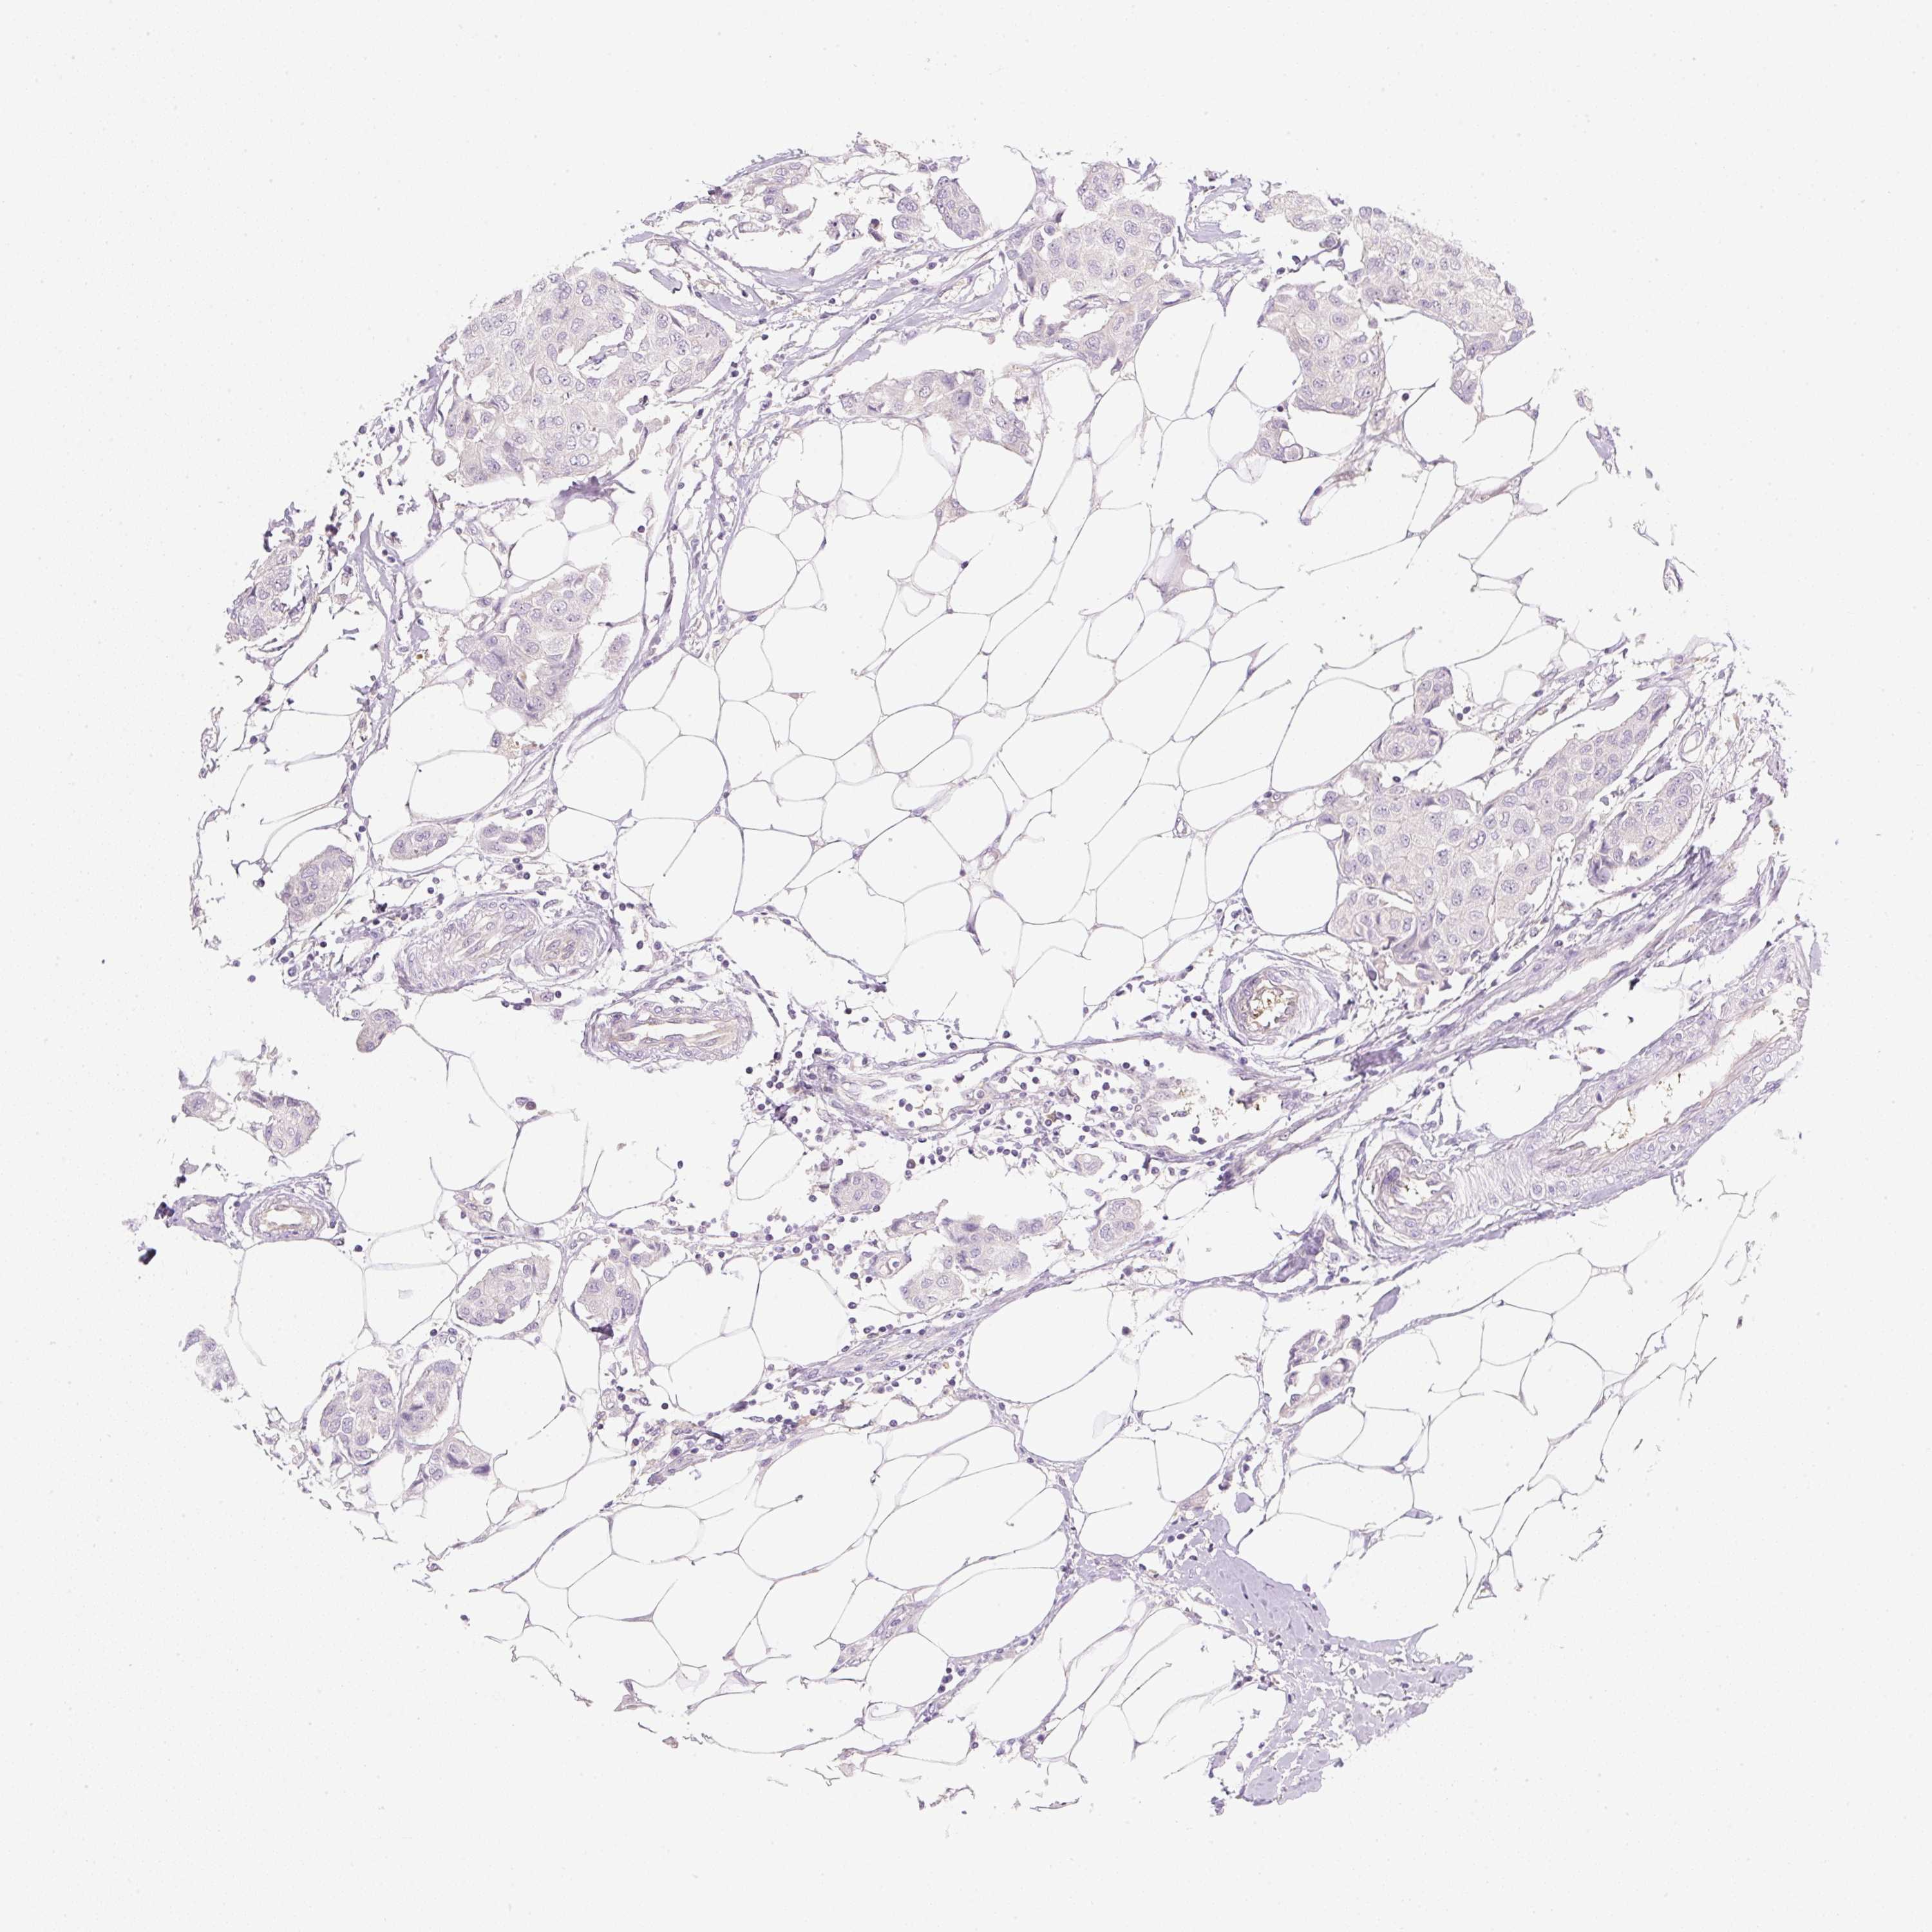

CANCER BREAST CANCER Show tissue menu

BRCA TCGA BRCA VALIDATION PROTEIN EXPRESSION